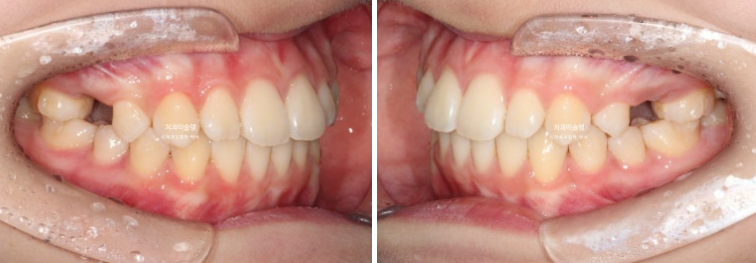

24.04

앞니가 유독 사이즈도 크고 아래로 내려와 있습니다.

측면에서 보면 뻗쳐서 튀어나와있죠

안모로 보면 앞니 돌출때문에 입이 잘 다물어지지 않는 입술부전증과 호두주름 (호두턱)이 관찰됩니다.

24.09

24년 9월까지 6개월간 첫세트 20개 장치를 모두 낀 후 모습입니다.

전반전이 끝났다고 표현할 수 있겠습니다.

내려와 있던 가운데 앞니 두 개는 위로 올라가면서 높낮이가 맞아졌고

앞니돌출은 개선이 되었습니다.

그 사이 남아있던 유치가 빠지고 영구치가 잘 나오고 있습니다.